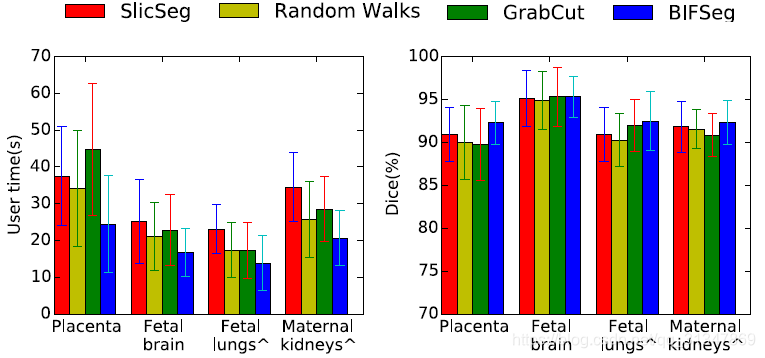

给出同样的 bounding box,作者将 P-Net 和之前的 FCN、U-Net 进行比较(2D分割),将 PC-Net 和 DeepMedic、HighRes3DNet 进行比较(3D分割)。

比较 BIFSeg 和 1)P-Net/PC-Net 的初始分割结果;2)用 CRF 处理之后的分割结果;3)BIFSeg(-w) 的分割结果(基于 Eq(1),所有像素的权重 w ( i ) = 1 w(i) = 1 w(i)=1),以及其他交互式分割方法:用于 2D 分割的 GrabCut,SlicSeg,Random Walks;用于 3D 分割的 GeoS,GrowCut,GrabCut 3D

1. 2D 图像分割

(4)与其他交互式分割方法的比较:

BIFSeg 可以实现花费更少的用户时间,但精度上与其他方法相近或更高。